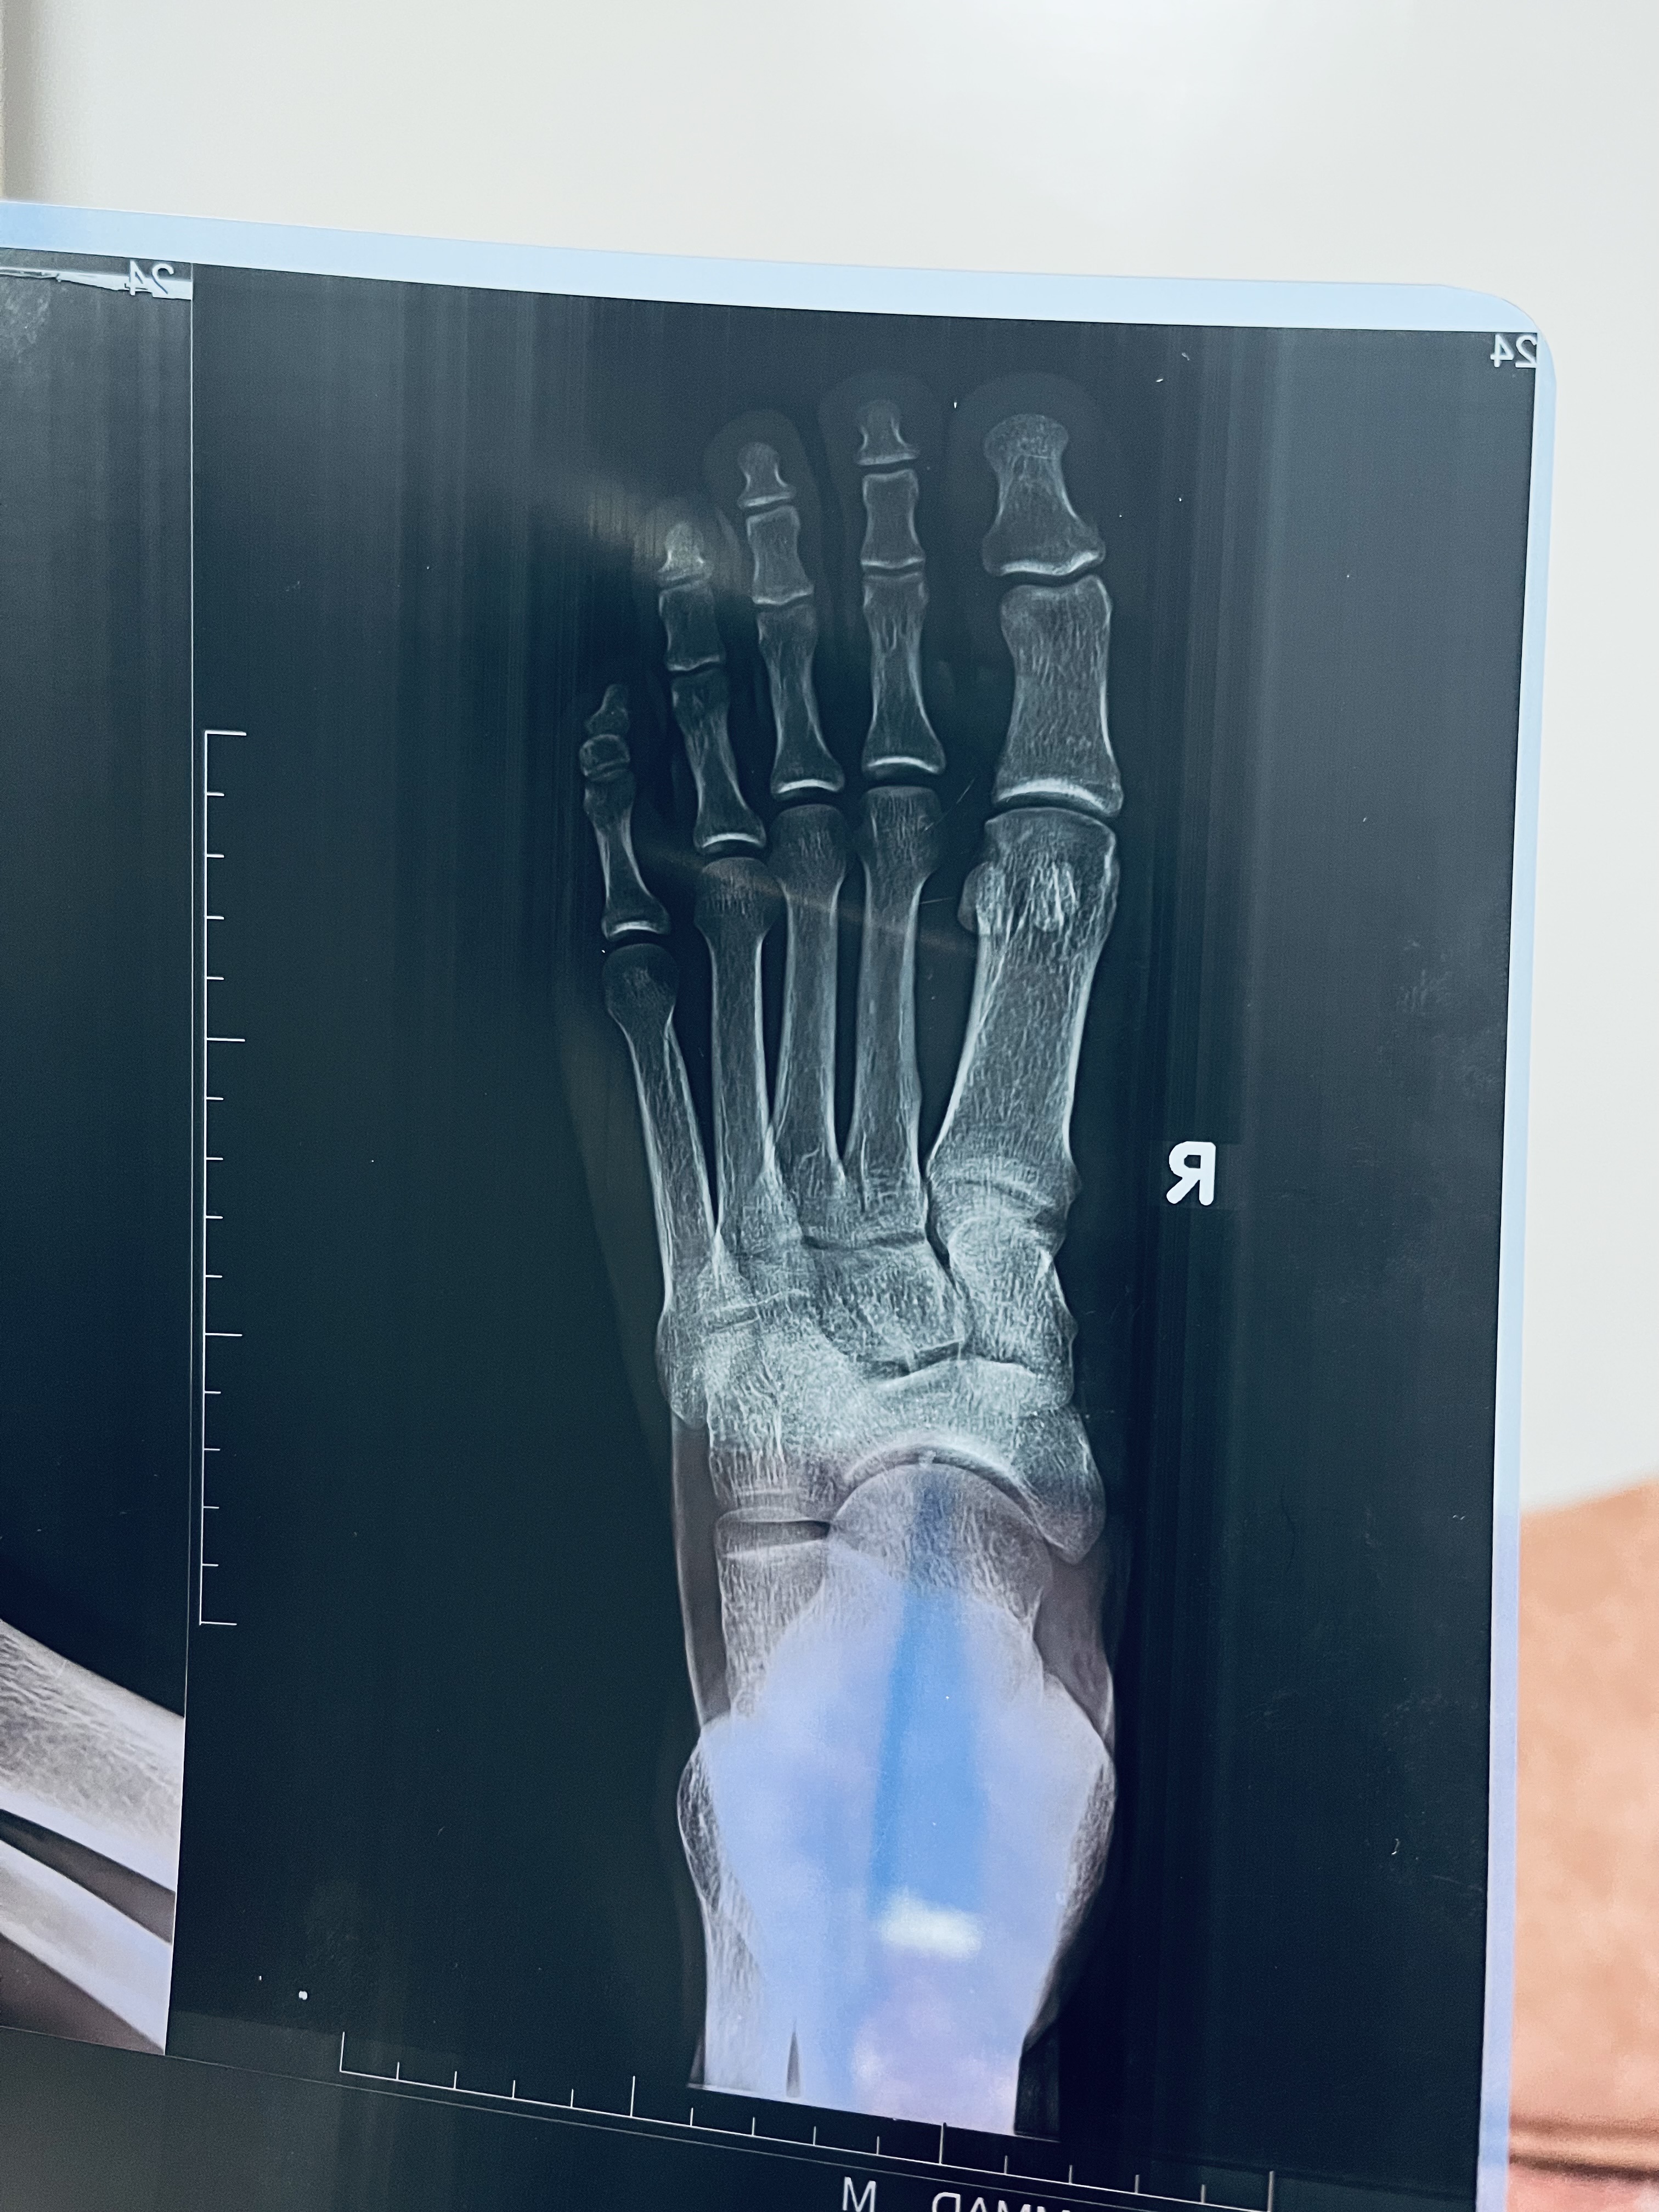

وجع تحت الظافر في الاصبع الاكبر في الرجل اليمني